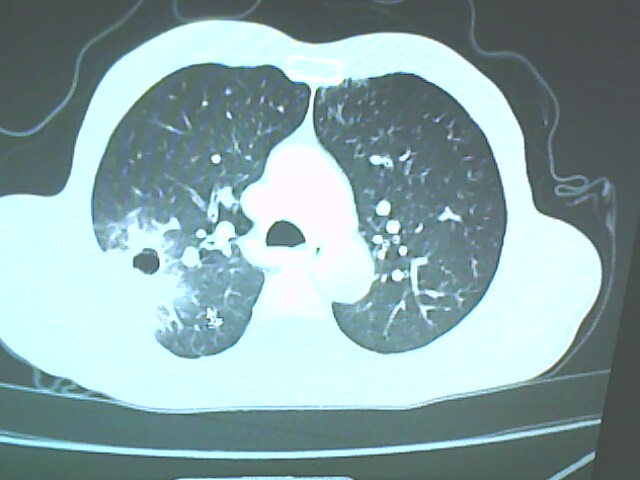

考虑癌性空洞可能性大,空洞内壁不规则,病灶周围模糊,分叶、有毛刺

考虑癌性空洞可能性大,空洞内壁不规则,病灶周围模糊,分叶、有毛刺。

空洞内壁不规则,病灶周围模糊,分叶、毛刺呈日光放射状,突然截断,支持考虑癌性空洞

考虑右肺上叶后段周围型肺癌并癌性空洞形成。

考虑癌性空洞可能性大,内壁不规则,洞壁薄厚不均呈结节状突起,边缘模糊,分叶,毛刺

典型癌性空洞(偏心性,壁厚薄不均,内壁不光整),周围毛刺较僵硬,且有刺突征和血管聚集征